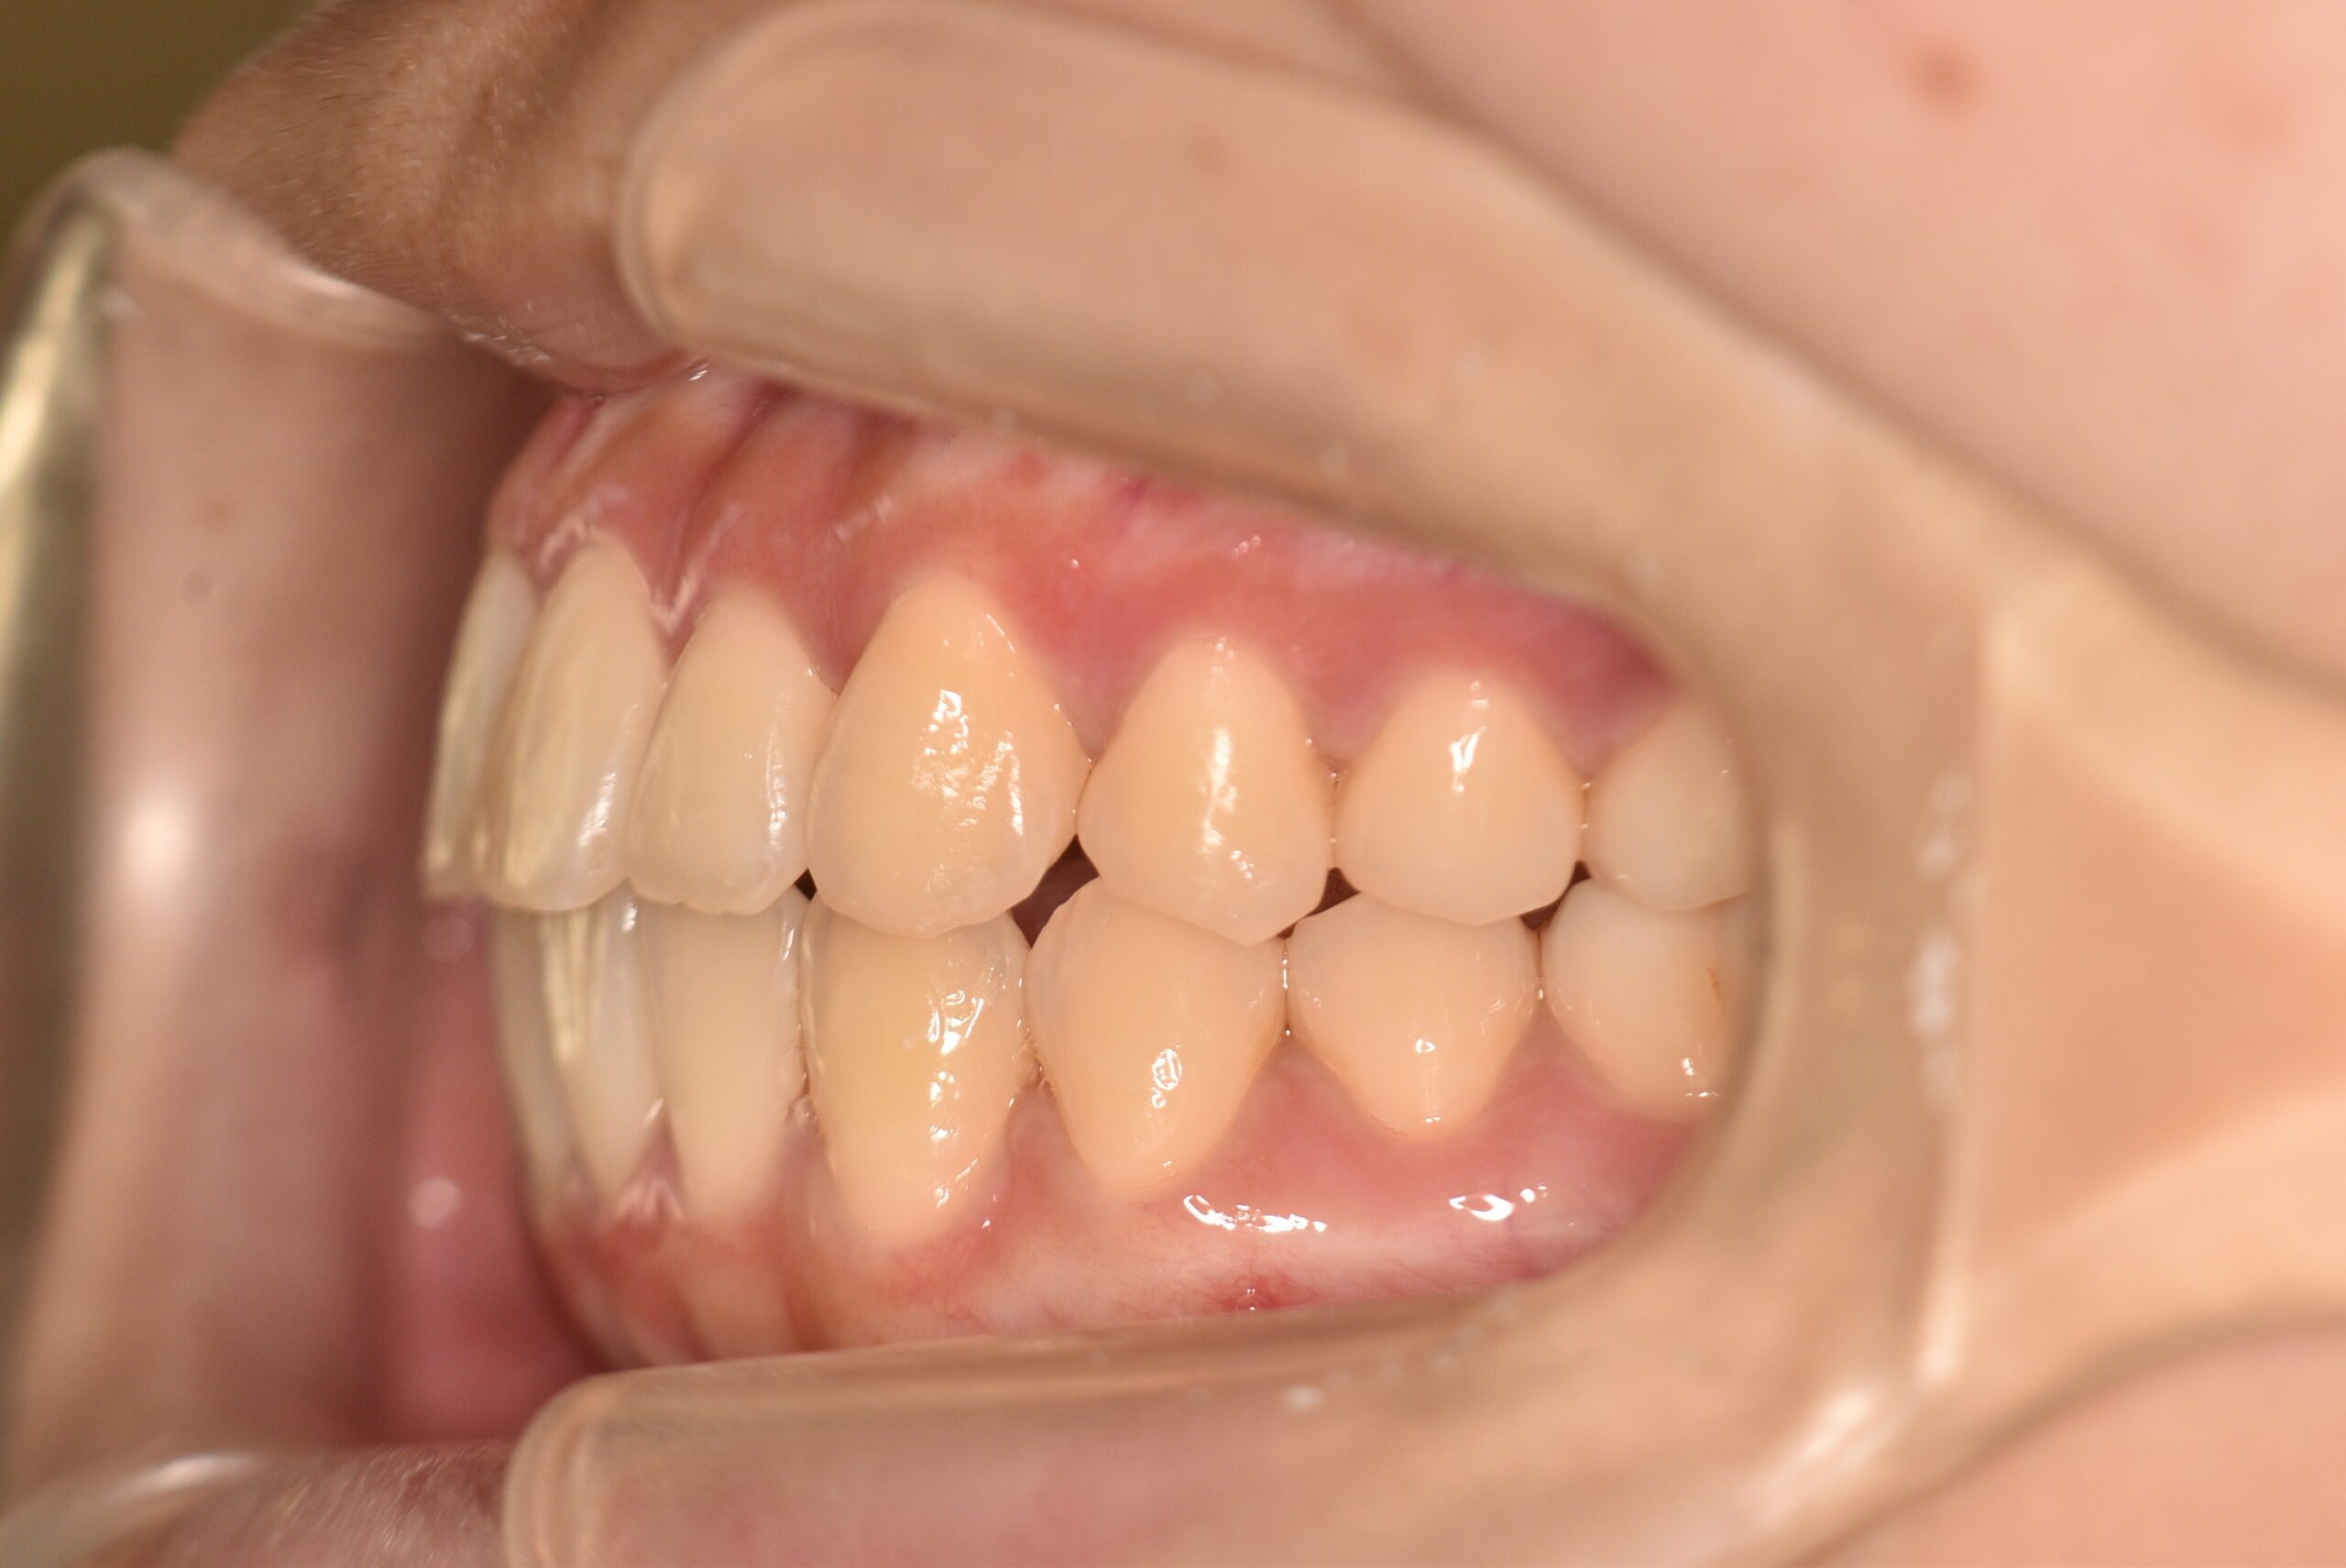

叢生(非抜歯)[2704]

動的治療終了時

治療内容の詳細 初診時17歳の女性で、かみ合わせが悪く少しガタガタしていることをを気にされ来院されました。

検査の結果、上下顎叢生を伴うアングル1級不正咬合と診断しました。

治療としては、非抜歯の上、マウスピース型矯正装置(インビザライン)で歯の配列を行いました。

治療期間は、1年10ヶ月でした。